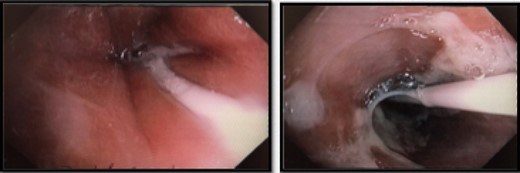

Interval gastroscopy in 2 weeks showed healing mucosal ischemia with slough from 27–30 cm (Fig. 3). Clear fluids were commenced and gradually upgraded to normal diet. Follow-up CT showed no contrast extravasation within posterior mediastinum (Fig. 4) and gastroscopy in 8 weeks showed healed esophagus.

CT scan at 2 weeks showing no contrast extravasation in posterior mediastinum.